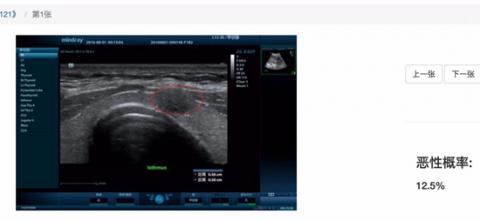

AI诊断甲状腺结节是否为恶性肿瘤

这是一场读片竞赛。与往常不同的是,人工智能(AI)要和医生一决高下。一家远程医学教育平台"心医学院"全程直播。"人类战队"需要拿出最快的速度,凭肉眼揪出深湖中的"怪兽",找到阴影处的结节,并判断是否为恶性肿瘤。

医生抬起头,紧绷的身体放松下来。大家似乎都明白,在速度上,人类本就不占优势。但结果还是让许多人吃了一惊。第一轮比赛中,AI与一位从业30年的超声科医师得分相同。两轮比赛厮杀下来,AI读片准确率高达73%,比人类医生团队的平均得分还要高。

季红的团队给视诊通AI"喂"了上千套甲状腺结节超声图片。这些病例来自北京友谊医院超声科,全都经过医学"金标准"检验确诊。医生事先标记出结节区域,技术人员对图片做一定的技术处理,接下来便得靠AI自个儿消化。

回归现实,AI诊断并非遥不可及。季红希望,未来实现在微信平台上辅助诊断。扫一个二维码,将疑似甲状腺结节、肺癌、乳腺癌等影像报告上传,AI立马便能告诉你,是恶性肿瘤的概率有多高。